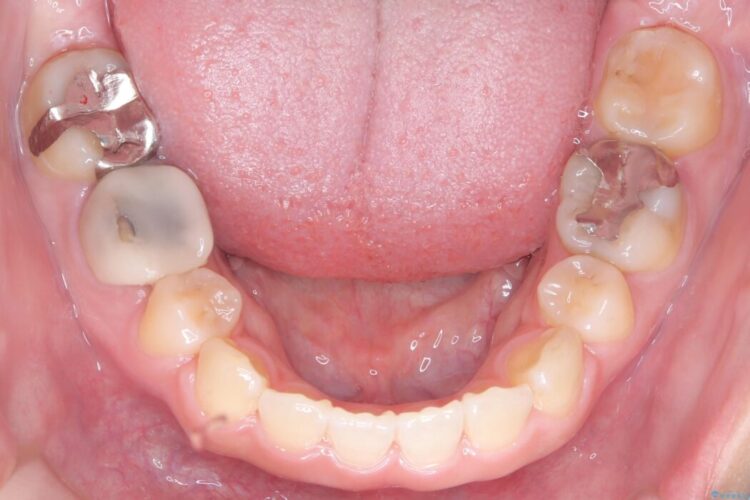

精密検査の結果、前歯を大きく後退させるスペースが必要と診断しました。

「前歯を下げたい」という患者様の強いご希望に応えるため、上下左右の第一小臼歯を抜歯。そのスペースを利用し前歯を奥へ移動させる治療計画を立案しました。

今回の矯正治療では、前歯を大きく後退させるスペースを確保するため、計画通り上下左右の第一小臼歯を抜歯しました。